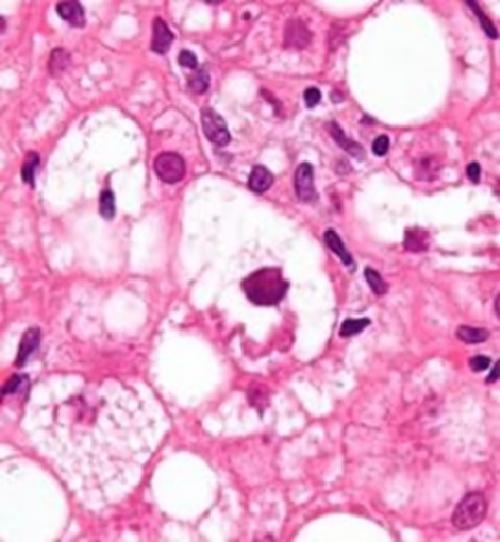

Клетки поражённого органа

Ожирение печени алкоголика или, по-научному, гепатоз, представляет собой патологию, в результате которой происходит трансформация нормальной и здоровой ткани печени в жировую, при этом, сильно поменяв структуру и состояние органа. Данное заболевание можно отнести к рефлексивной реакции организма на отрицательное действие ряда факторов, главным из которых считается токсическое свойство, вызванное распитием спиртосодержащей продукции. Поэтому частый прием спиртного ведет к быстрому обрастанию печени жиром, лечение которой будет трудным и долгим. Важно: помимо печени, при распитии алкоголя происходит поражение жиром и других органов, к примеру, поджелудочной железы.

Патогенез в органе развивается из-за содержания в нем большого количества триглицеридов в гепатоцитовых клетках, что вынуждает нормальные и здоровые клетки заменяться на жировые.